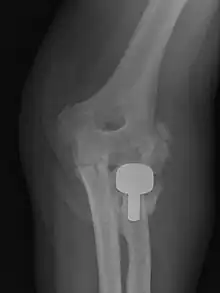

Prophylactic radiation therapy for the prevention of heterotopic ossification has been employed since the 1970s. A variety of doses and techniques have been used. Generally, radiation therapy should be delivered as close as practical to the time of surgery. A dose of 7-8 Gray in a single fraction within 24–48 hours of surgery has been used successfully. Treatment volumes include the peri-articular region, and can be used for hip, knee, elbow, shoulder, jaw or in patients after spinal cord trauma.

Single dose radiation therapy is well tolerated and is cost effective, without an increase in bleeding, infection or wound healing disturbances.[6]